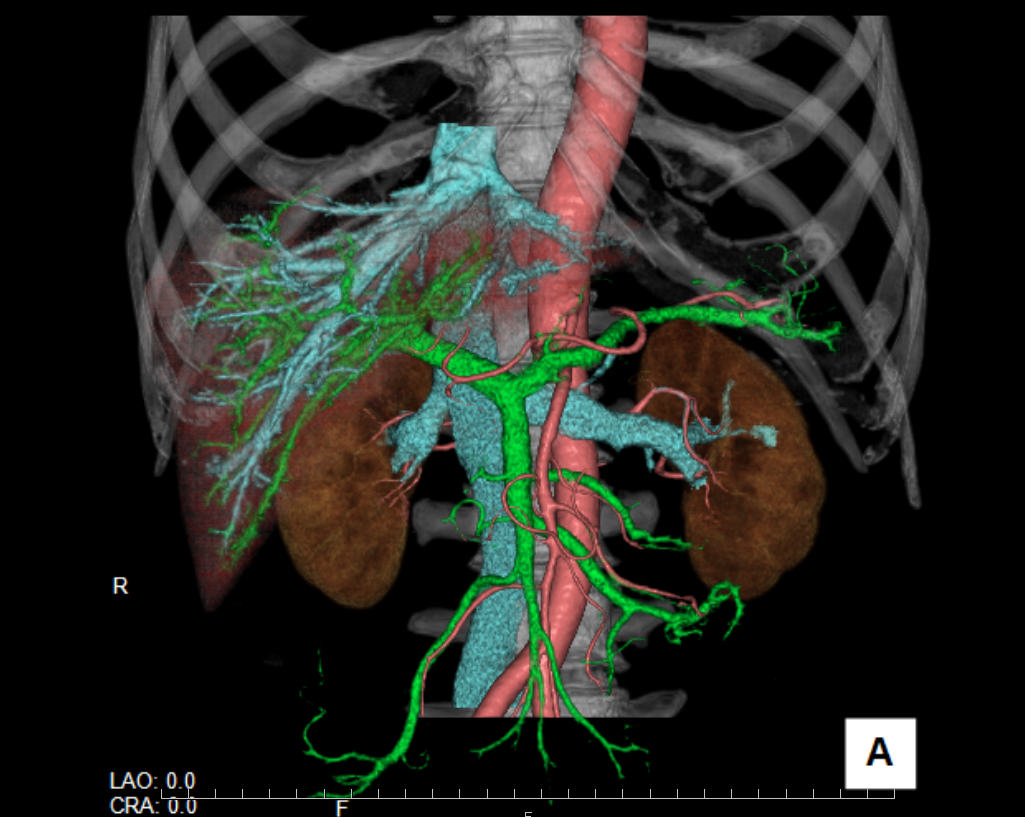

撮影された画像データを⽤いて、様々な⾓度から体を観察できます。よく使われるのは、体を横からみた⽮状断(サジタール画像)、体を正⾯からみた冠状断(コロナール画像)です。また3D画像も作成可能です。⼿術や検査結果の説明に使⽤されています。

CTの検査には、静脈から造影剤を注⼊して撮影をする造影検査があります。造影剤を 使⽤することで、⾎管や臓器の⾎流の変化などを検査できます。また、⽩と黒の濃淡の差がより強調されることで、正常部位と腫瘍などを⾒分けることにも⽤いられます。